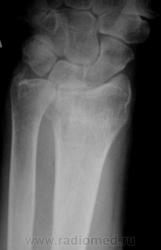

Травма. Пациент направлен на рентгенографию лучезапястного сустава.

луча в типичном месте. А вот шиловидный отросток похоже тоже сломался?